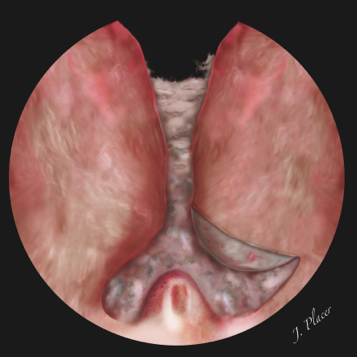

El siguiente paso de la cirugía consiste en la disección de los lóbulos prostáticos laterales. El movimiento de giro y basculación lateral que tiene que hacerse con el endoscopio en esta parte de la cirugía motiva que posiblemente sea más cómodo comenzar por el lóbulo lateral izquierdo si el cirujano es diestro. Dejando fija la vaina externa del resectoscopio a la altura del borde superior del verumontanum practicamos una incisión sobre el lóbulo apical izquierdo hasta llegar a la cápsula prostática (Figura 6). La incisión transversa que realizamos al principio de la cirugía a la altura del borde superior del verumontanum facilita en gran manera hallar el plano de disección adecuado. Es importante hacer varias incisiones cortas (<1 cm) pero suficientemente profundas para poder llegar al plano de la cápsula prostática. Al mismo tiempo que realizamos las incisiones tenemos que hacer un movimiento de basculación lateral del resectoscopio que nos permita introducirlo por debajo del lóbulo apical que estamos liberando. Esta maniobra permite levantar el lóbulo apical y despegarlo de la cápsula prostática. El error que más habitualmente se comete en esta parte de la cirugía, sobre todo cuando los lóbulos apicales descienden caudalmente con respecto al verumontanum, consiste en hacer unas incisiones demasiado superficiales y no llegar al plano de la cápsula prostática, hecho que conduce a que la enucleación sea incompleta y a través del adenoma. La presencia de adenoma apical residual suele dificultar los movimientos de basculación lateral del resectoscopio durante la disección del resto del lóbulo lateral. Además, si no se alcanza el plano de la cápsula prostática y la enucleación se realiza a través del propio adenoma, suele ser más difícil orientarse endoscópicamente y saber cuál es el lugar por el que ha de proseguir la disección. Por el mismo motivo suele ser más difícil realizar una buena hemostasia si la enucleación se realiza a través del adenoma que si se hace siguiendo el plano de la cápsula prostática.

Figura 6. Disección del lóbulo apical izquierdo